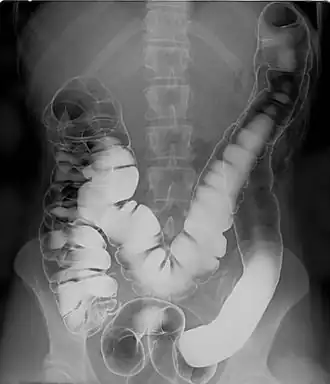

Barium sulfate (digestive system)

Barium sulfate is mainly used in the imaging of the digestive system. The substance exists as a water-insoluble white powder that is made into a slurry with water and administered directly into the gastrointestinal tract.

- Barium enema (large bowel investigation) and DCBE (double contrast barium enema).

Barium sulfate, an insoluble white powder, is typically used for enhancing contrast in the GI tract. Depending on how it is to be administered the compound is mixed with water, thickeners, de-clumping agents, and flavourings to make the contrast agent. As the barium sulfate does not dissolve, this type of contrast agent is an opaque white mixture. It is only used in the digestive tract; it is usually swallowed as a barium sulfate suspension or administered as an enema. After the examination, it leaves the body with the feces.